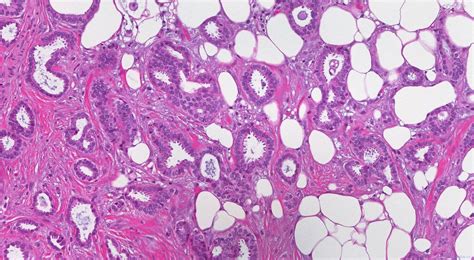

Alright, so what exactly is invasive right breast carcinoma ? Basically, it’s cancer that starts in the right breast and has spread beyond the ducts or lobules where it originated. It’s considered “invasive” because it has broken through the boundaries of the tissue where it began, potentially spreading to other parts of the body. There are various types, with the most common being invasive ductal carcinoma and invasive lobular carcinoma . The former starts in the milk ducts, while the latter begins in the milk-producing lobules. Understanding the type helps doctors determine the best course of treatment. The right breast is simply the location where this process is taking place. This localization is important, as it helps determine the extent of the cancer and guide treatment decisions, like surgery, radiation, and medication. The term “carcinoma” itself refers to a cancer that originates in the epithelial cells – the cells that cover the surfaces of the body, including the breast tissue. This means that when we’re talking about invasive right breast carcinoma , we’re referring to a very specific type of cancer that must be accurately identified and documented for proper care. Guys, remember that early detection is key, and regular screenings are super important. If you feel anything unusual, don’t hesitate to see a doctor! It’s better to be safe than sorry, right?

For invasive carcinoma of the right breast , the code usually starts with the prefix “C50”. Then, there are further codes that specify the exact location within the breast. So, a code might specify the upper-outer quadrant of the right breast, or it might specify the nipple and areola. The codes become more specific as doctors gather more information about the cancer. Another important consideration is the type of cancer. For example, the code will likely specify whether it’s invasive ductal carcinoma or invasive lobular carcinoma. Each type of cancer has its specific codes, which allows for accurate diagnosis. In addition to the location and type, the stage of the cancer is crucial. The stage of the cancer indicates how far the cancer has spread. The codes are grouped by the different stages, from Stage 0 (carcinoma in situ) to Stage IV (metastatic cancer). The specific code used will vary, reflecting the stage of the cancer. The codes also specify whether the cancer has spread to the lymph nodes. Lymph node involvement is a key factor in determining treatment and prognosis. Another thing these codes can tell you is whether the cancer is hormone receptor-positive or HER2-positive. These receptors help determine which treatments will work best.